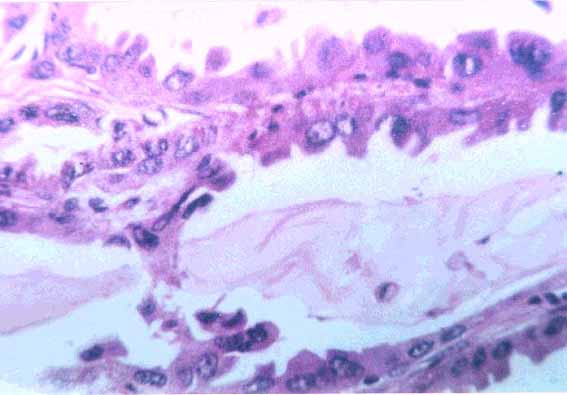

fig. 3

Figura 3. Microfotografía 2. Se observan algunos sectores con mucosecreción